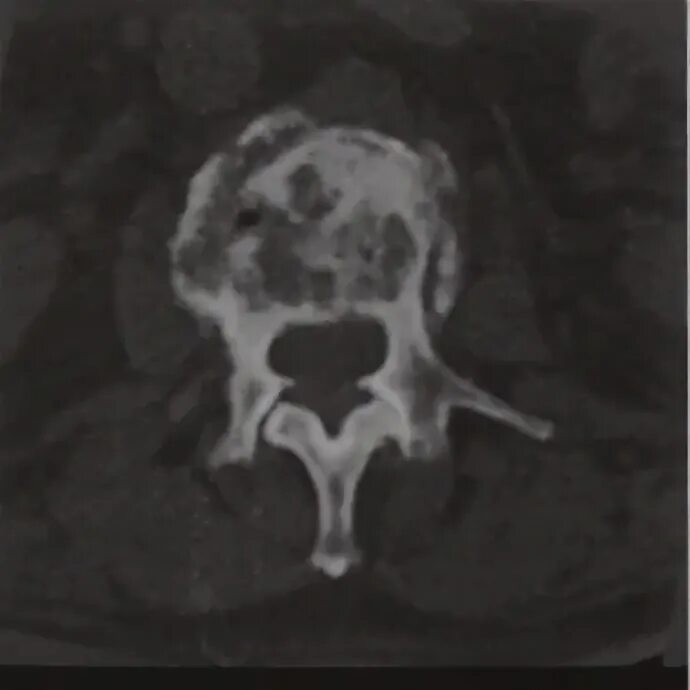

Метастазы костей мрт